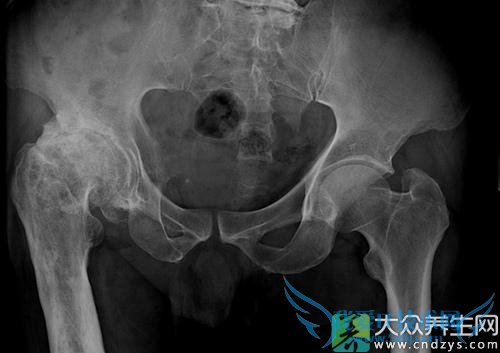

2 .XÏß±íÏÖ£º¹Ø½Ú¼ä϶±äÕ­ÉõÖÁÏûʧ£¬¹Ø½Ú±ßÔµ¹Ç´ÌÐγɣ¬¾Ö²¿Èí¹ÇϹÇÖÊÃܶÈÔö¼Ó£¬Í·¾ÊÄÒÐÔ±äÒÔ¼°¹É¹ÇÍ·ÃܶȺÍÐÎ̬Éϵĸı䡣